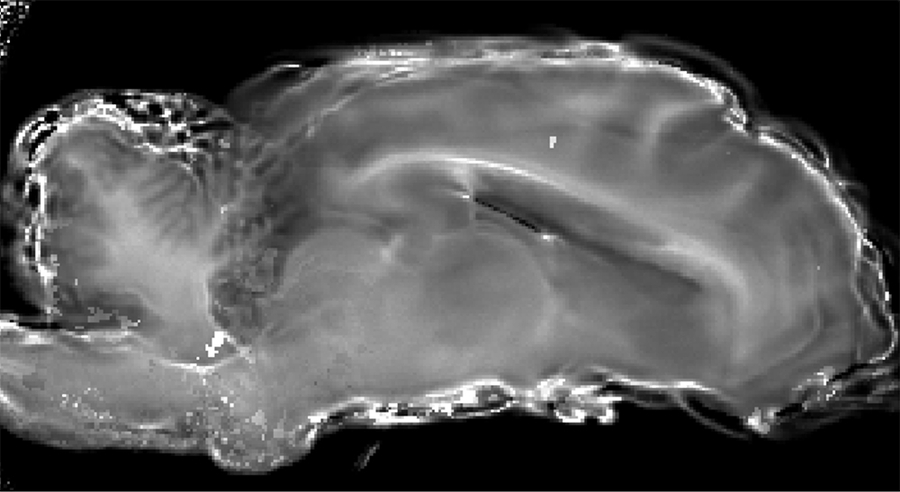

Our research is centered on physical ultrasonics. We study the ultrasonic properties of soft matter, including mammalian soft tissue and tissue-mimicking phantoms. We also study the physical properties of complex fluids, such as micellar fluids, using ultrasound and other mechanical waves as tool. Development and characterization of tissue-mimicking phantoms is also part of our work.